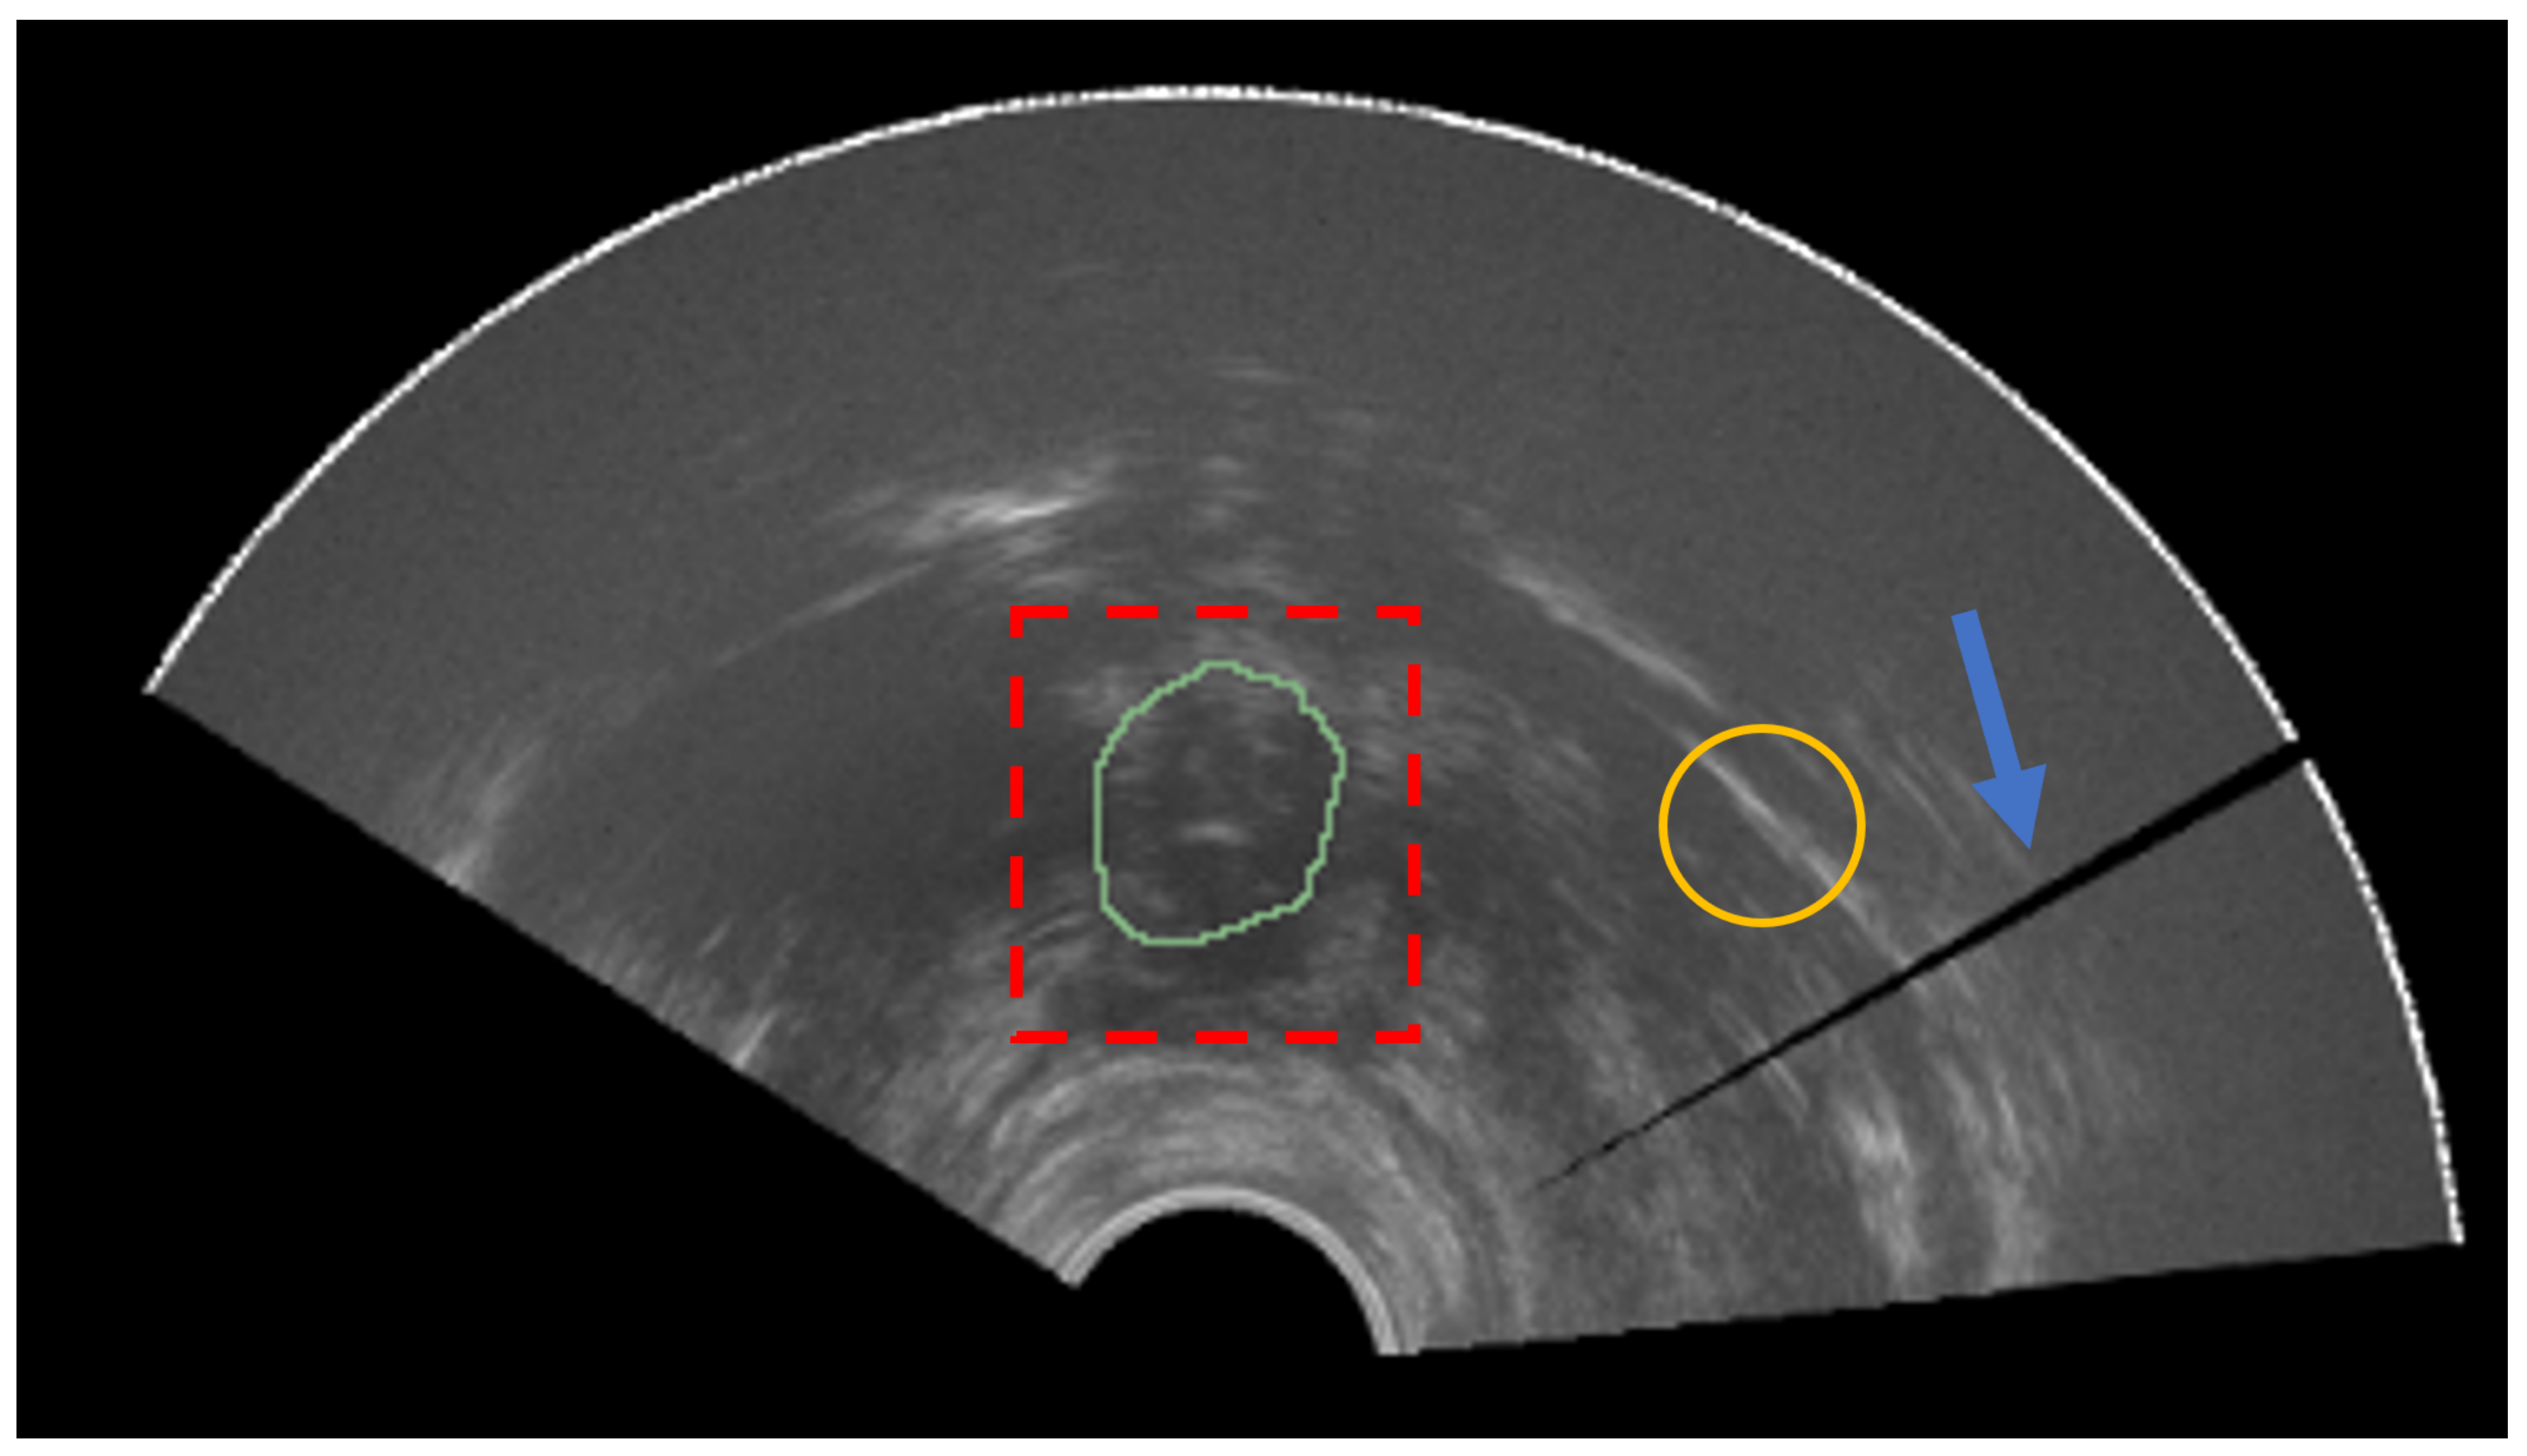

Prostate cancer is a major health problem and represents the most common cancer in the male population, accounting for 18.5% of all the cancers diagnosed in humans [1]. The number of new cases worldwide passed 1,275,000 and caused approximately 360,000 deaths in 2018 alone (3.8% of all deaths caused by cancer in men) [2]. Numerous imaging modalities are employed for prostate cancer diagnosis, treatment, and follow up. Transrectal ultrasound (TRUS), magnetic resonance imaging (MRI), and computed tomography (CT) are the most common employed imaging modalities [3]. Each technique provides different information and is used for several divergent clinical scopes. During biopsy procedures, TRUS is commonly employed since it is an inexpensive, portable, and real-time methodology [4]. MRI is mainly adopted for diagnosis and treatment planning [5]. In fact, this modality has better soft tissue contrast and allows more efficient lesion detection and staging in patients affected by prostate cancer. As can be seen from Figure 1, the TRUS images suffer from problems such as speckle, low contrast, and shadow artifacts [6]. Calcification and acoustic shadowing make the automatic segmentation of prostate region a very complex task [7]. The prostate usually appears like a hypoechoic mass encompassed by a hyperechoic region [8]. CT scans are useful in determining if prostate cancer has spread to bone tissues or to assess the effectiveness of the brachytherapy [9,10].

Figure 1.

Prostate apex (ground-truth mask in green) is not easily distinguishable from the rest of the image (red dashed box). The yellow circle represents an example of a region with low signal-to-noise ratio. The blue arrow denotes a shadow artifact.